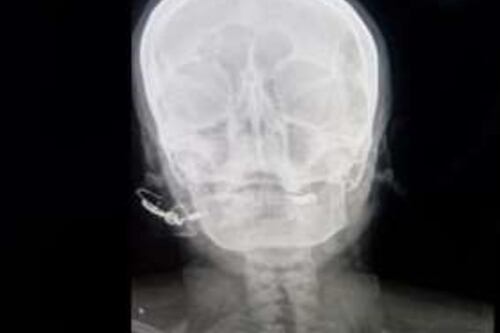

Curandero inserta clavo en cráneo de mujer embarazada para dar a luz a un varón

El incidente, que tuvo lugar en Pakistán, se hizo público cuando se descubrió que la mujer había sido persuadida por un curandero, quien le prometió que el ritual le aseguraría el nacimiento de un hijo varón.